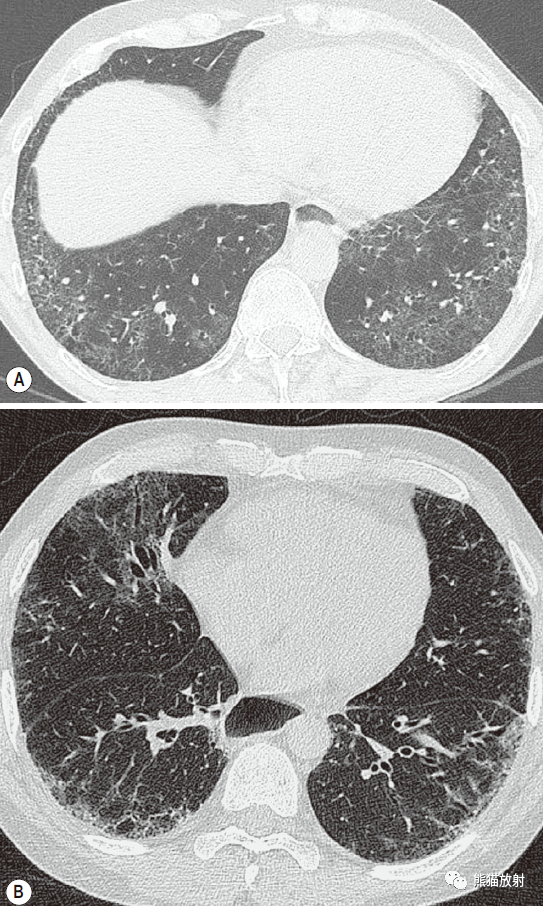

显微镜下多血管炎1例——病例回顾(五)

学术交流 | 系统性血管炎的肺部影像学表现及鉴别诊断

轴位hrct显示双肺多发结节,结节周边磨玻璃影(晕征).